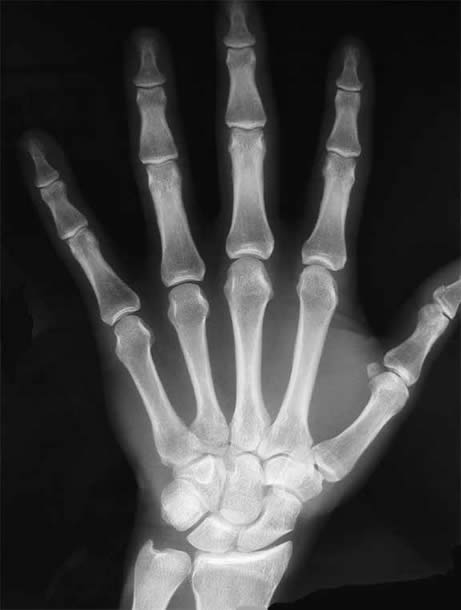

My first memory of such tests was an x-ray I had taken of my wrist after a hockey accident. As explained in the lecture, Rontegen’s early testing paved the way for doctors to have the ability to see my hand without actually making an incision. The thing that stuck with me more however was when Professor Vesna described Rontegen’s wife’s reaction to seeing her X-Ray, which was, “I can see my death”.

When skin is removed, the

bone is all our hand is left with

While I’ve looked at pictures of x-rays probably hundreds of times, never before had I considered it a preview of what was to come in life.